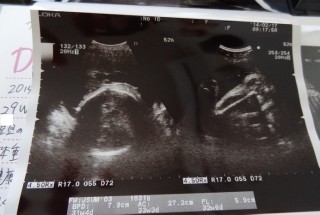

やっとはっきり見せてくれたシンボル!!

男の子確定です♪

細めで小さ目だけどとっても元気な我が子です。

推定体重1,800gくらい